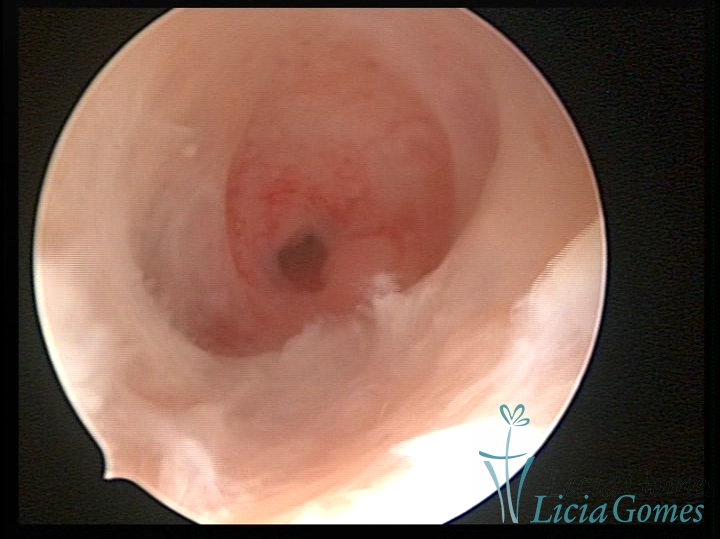

Septate uterus

It probably occurs by the lack of resorption on the middle line, in the merge of Müllerian ducts. The uterus is divided by a partial or total septum which is viewed as a crossbar, not covered by endometrium, which not bleeds when sectioned.

Complete septum when it occupies the whole extension of the cavity, dividing it into two hemicavities.

When this septum occupies only a part of the extension of the uterine cavity, it is considered as incomplete.